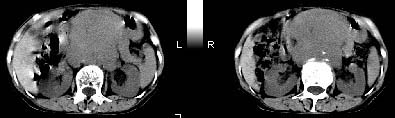

女:61岁.腹痛腹胀20天,行b超腹膜后实性占位.扫完后我查体发现患者右颈根部约3厘米类圆性包块,有移动{我考虑右颈根部包块是肿大淋巴结}.

ct:肝胃之间、胰头后、腹主a周围,融合而成团块状影,包绕血管,胰腺前移后缘分界欠清,与肝胃分界清,肿块未见明显强化,肝右叶后段小囊肿。

女:61岁.腹痛腹胀20天,行b超腹膜后实性占位.扫完后我查体发现患者右颈根部约3厘米类圆性包块,有移动{考虑右颈根部包块是肿大淋巴结}.

诊断:淋巴瘤>转移瘤。

肝胃之间、肝十二指肠韧带,胰头后、腹主a周围,融合而成团块状影,包绕血管[腹腔干、肠系膜上动脉,腹主动脉],胰腺前移后缘分界欠清,与肝胃分界清,肿块未见明显强化,肝右叶后段小囊肿。

考虑1淋巴瘤。2转移瘤。3恶性组织细胞瘤。